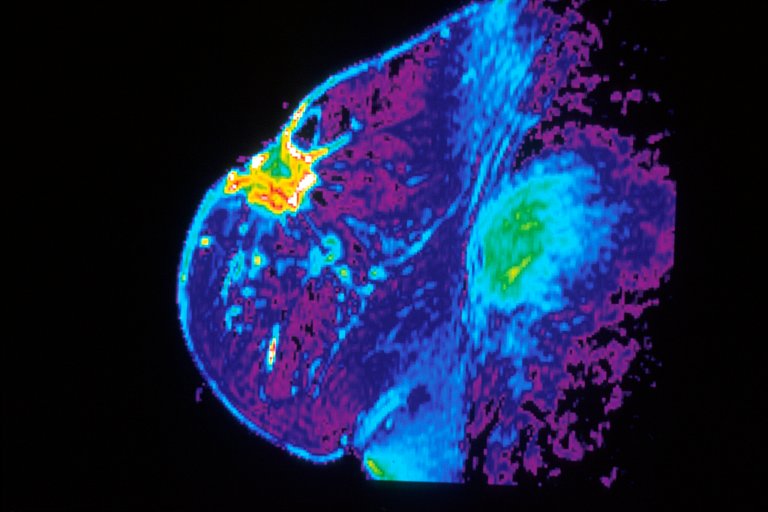

Diagnosing cancer can be a challenging task. Often, pathologists have to quickly decide whether a microscopic group of cells looks malignant or benign, or whether a small lump seen on a mammogram is suspicious. For this reason, pathologists go through four years and more of medical school and training. But it turns out that pigeons may one day be able to help out.

In another task, in which the pigeons were asked to detect cancerous breast masses on mammograms, the pigeons were only able to memorize the correct answer–they couldn’t look at a new image and determine whether that mass was cancerous or benign. This is challenging task for even a group of pathologists who (as part of the study), viewed the same masses, and were only accurate 80 percent of the time.